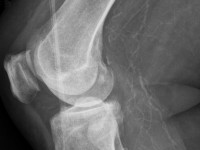

röntgenfoto's is vaak uitgebreide verkalking te zien: het complete arteriële

stelsel is verkalkt en zichtbaar, alsof het een contrastfoto was. De huid

![Calciphylaxis cutis bij nierinsufficiëntie en secundaire hyperparathyreoïdie (click on photo to enlarge) [source: www.huidziekten.nl] Calciphylaxis cutis bij nierinsufficiëntie en secundaire hyperparathyreoïdie](../../../images/calciphylaxis-3z.jpg) |

![Calciphylaxis cutis bij nierinsufficiëntie en secundaire hyperparathyreoïdie (click on photo to enlarge) [source: www.huidziekten.nl] Calciphylaxis cutis bij nierinsufficiëntie en secundaire hyperparathyreoïdie](../../../images/calciphylaxis-4z.jpg) |

| calciphylaxis cutis |

calciphylaxis cutis |